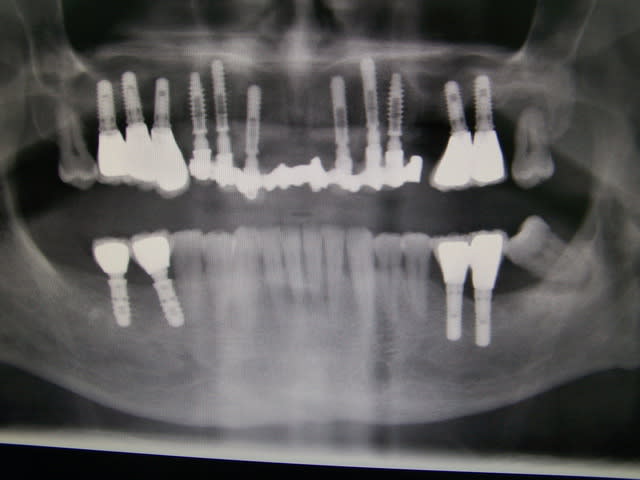

jeudi

extraction implantation mise en charge immédiate

mandibule

vendredi

maxillaire

Wilson, sur l’image jointe il y a l’OTP pré- opératoire, les dents extraites, une modélisation 3D du site et l’OTP post-opératoire avec les implants et prothèses posée en 1 temps chirurgical.

Quel aurait été ton plan de traitement ?

Le praticien traitant ne se souciant pas des problèmes paro existant, il ne devrait pas avoir grande peine à ne pas voir les problèmes infectieux peri-implantaires qui se manifesteront dans peu de temps (regarde l'implant en 26, tu crois que ça l'à choqué !!)